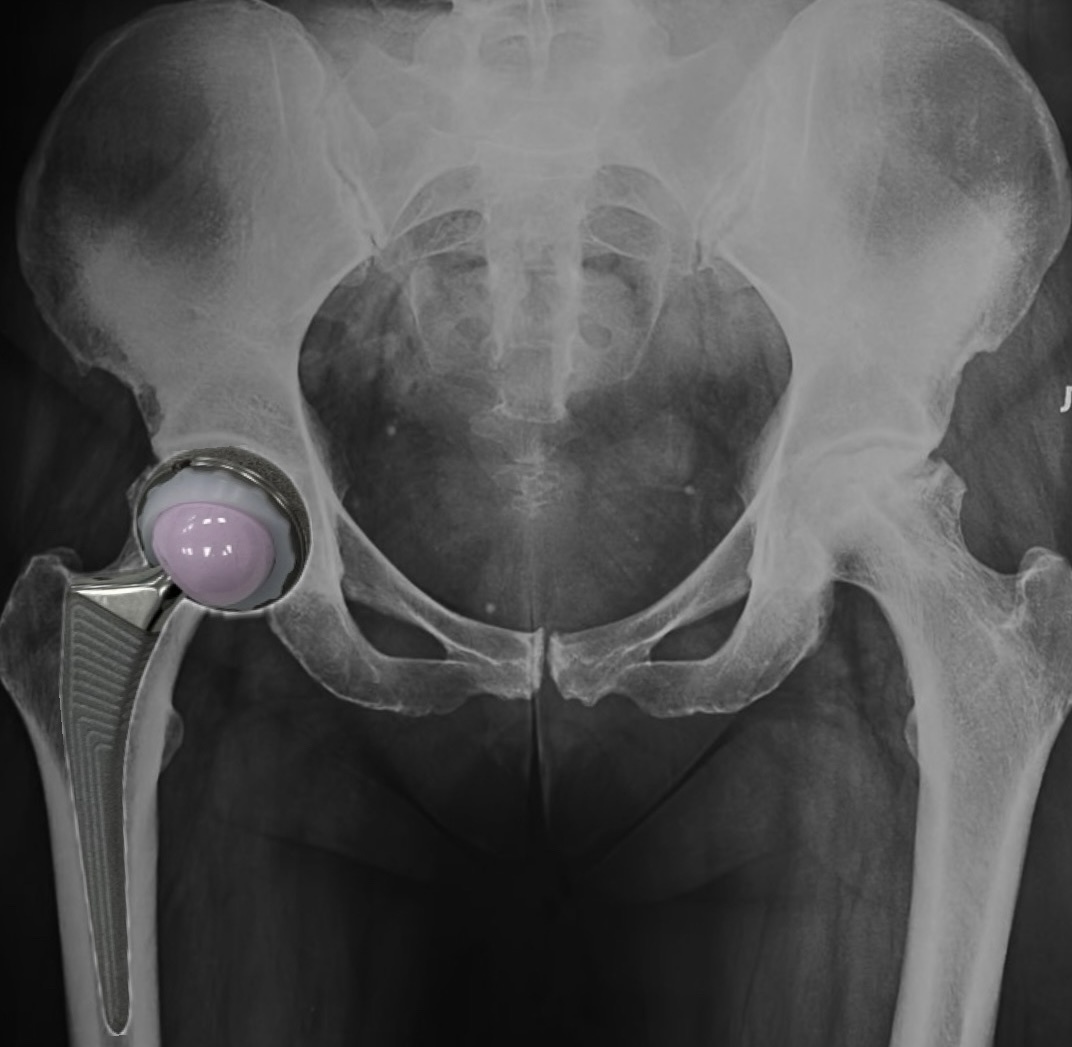

Пара трения

Одним из определяющих факторов долговечности импланта является выбор пары трения — материалов, контактирующих в суставной поверхности. Традиционно применялись пары «металл–полиэтилен», «керамика–керамика» и «керамика–полиэтилен». Последняя, особенно в форме «керамика + высокосшитый полиэтилен (HXLPE)», представляет собой компромисс между низким износом и относительной надёжностью. Суть вопроса выбора, заключена в одном простом понятном механизме: высокая скорость износа с образованием микрочастиц, приводит к остеолизу и асептическому расшатыванию компонентов. Почему керамика? В экспериментальных исследованиях отмечается, что керамика снижает образование абразивных частиц третьего тела и менее подвержена повреждениям при попадании мелких частиц в суставную щель. В отличие от металлических головок, керамические не стимулируют коррозийные процессы, что исключает проблему ионного загрязнения вокруг протеза. А за счет более гладкой поверхности при сочетании с использованием HXLPE - совре

В экспериментальных исследованиях отмечается, что керамика снижает образование абразивных частиц третьего тела и менее подвержена повреждениям при попадании мелких частиц в суставную щель. В отличие от металлических головок, керамические не стимулируют коррозийные процессы, что исключает проблему ионного загрязнения вокруг протеза. А за счет более гладкой поверхности при сочетании с использованием HXLPE - современных типов вкладышей-значительно уменьшает образование полиэтиленовых частиц при трении двух твердых тел, что снижает риск остеолиза.